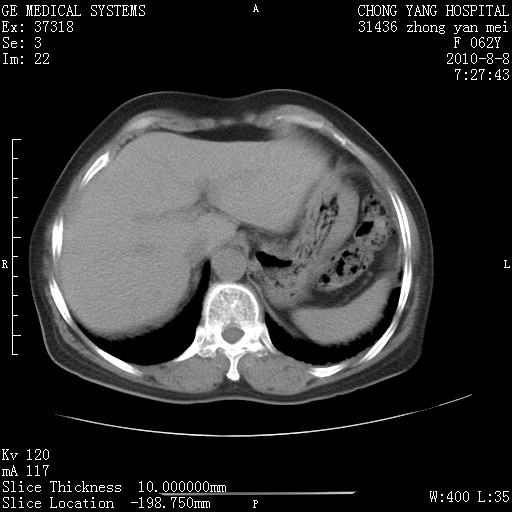

另见右乳腺似有小钙化灶,建议进一步检查。

1.肺间质纤维化.

2.纵隔淋巴结肿大。

3.迷走右锁骨下动脉。